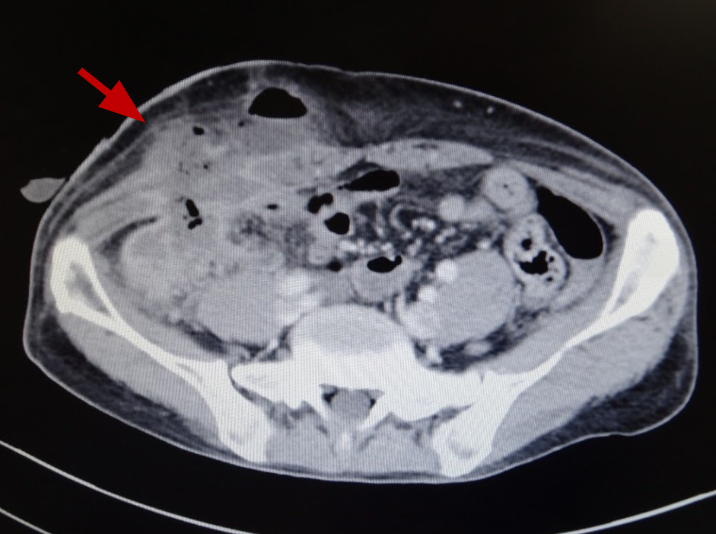

[Figure caption and citation for the preceding image starts]: Amoebic appendicitis with skin fistula two weeks after appendectomy (enhanced computed tomography).Original photo from National Center for Global Health and Medicine, Tokyo, Japan. [Citation ends].

Less common extraintestinal manifestations are peritonitis from perforation of the intestine, which sometimes mimics acute appendicitis, and pleural or pericardial effusions from direct extension of a liver abscess and brain abscess (almost all patients with brain abscess due to E histolytica also have a liver abscess).[1][2][3][4][5][6][8][9] Amoebic acute appendicitis is also a possible but rare manifestation of amoebiasis; amoebic appendicitis is more likely to be complicated than non-amoebic appendicitis.[9]